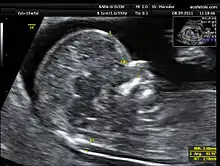

Translucência nucal

Uma das grandes contribuições da pesquisa ultra-sonográfica do final do século 20 foi a demonstração de que o acúmulo excessivo de fluido na nuca do feto, conhecido como translucência nucal (TN), está correlacionado com anomalias cromossômicas, malformações fetais e síndromes genéticas.

Desde o início dos anos 90, diversos estudos com pequenas casuísticas e com populações de alto risco demonstraram associação entre o aumento da espessura da TN, entre a 11ª e a 13ª semana e 6 dias, e a presença de anomalias cromossômicas. Os mecanismos fisiopatológicos que explicam esse marcador ultra-sonográfico transitório ainda não estão bem estabelecidos. Alguns eventos que ocorrem nessa época da gestação poderiam eventualmente esclarecer o acúmulo transitório de líquido na região da nuca do feto, que é atribuído a alterações da drenagem linfática fetal e/ou, particularmente, a distúrbio hemodinâmico do feto devido à insuficiência cardíaca fetal.